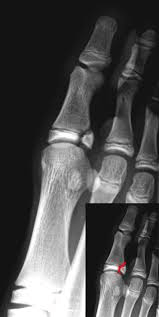

Identify this type of injury? What type is it (I-IV) And what is the appropriate treatment?

What is an appropriate management of this Seymour fracture?

Open reduction, debridement of the fracture site, repair of associated nail bed laceration, and possible Kirschner wire fixation of the fracture across the DIP joint.